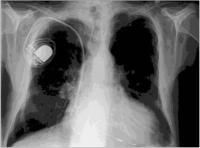

Biventrikulärer Herzschrittmacher

Abbildung 2: Biventrikulärer Schrittmacher im Thorax-Röntgen; auffällig ist, daß neben einer normalen Stimulationselektrode im rechten Vorhof und im rechten Ventrikel eine dritte Sonde über den Sinus coronarius an den linken Ventrikel herangeführt wird.